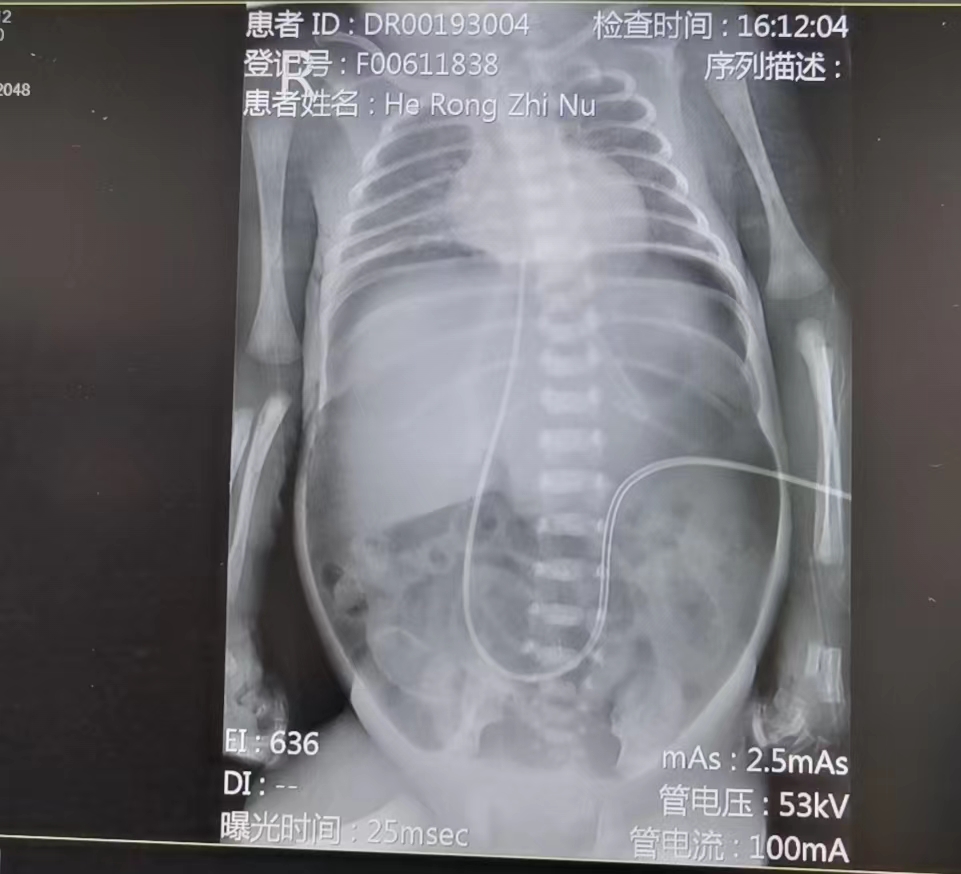

近日,一位出生仅3天800g的30周早产儿,因消化道穿孔由外省转运至我院新生儿科。患儿入院后立即完善相关检查,继续监测生命体征变化。在完善检查期间,患儿病情加剧。当即,联系小儿外科行急诊手术。术中探查在回盲部约5CM处,可见回肠壁上有两处破口,予以部分切除和缝合。王惠萍主任医师团队针对这位的超低出生体重儿个体情况制定了详细的治疗方案,对患儿病情实施各系统方面精细化管理,针对呼吸系统采取肺保护通气支持,积极进行抗感染治疗,制定营养支持治疗方案,同时做好各种突发情况应急救治预案等。医护人员争分夺秒,精准施治,术后重症超声精准指导容量管理,呼吸循环监测,各项指标均有好转。但宝宝仍需要闯一道又一道关卡,而这每一道关卡都布满了陷阱,稍有不慎就会前功尽弃。希望她能勇攀高峰,跨越艰难险阻。

新生儿消化道穿孔,其起病急、病情重、病死率高(极低出生体重儿发病率为4.5%~8.7%,病死率为20%~30%,超低出生体重儿病死率可高达30%~50.9%)。导致新生儿消化道穿孔原因很多,其中先天性消化道畸形和坏死性小肠结肠炎。导致的穿孔最为常见,主要的致死原因包括重症感染、多部位穿孔、就诊时间延迟以及早产等。